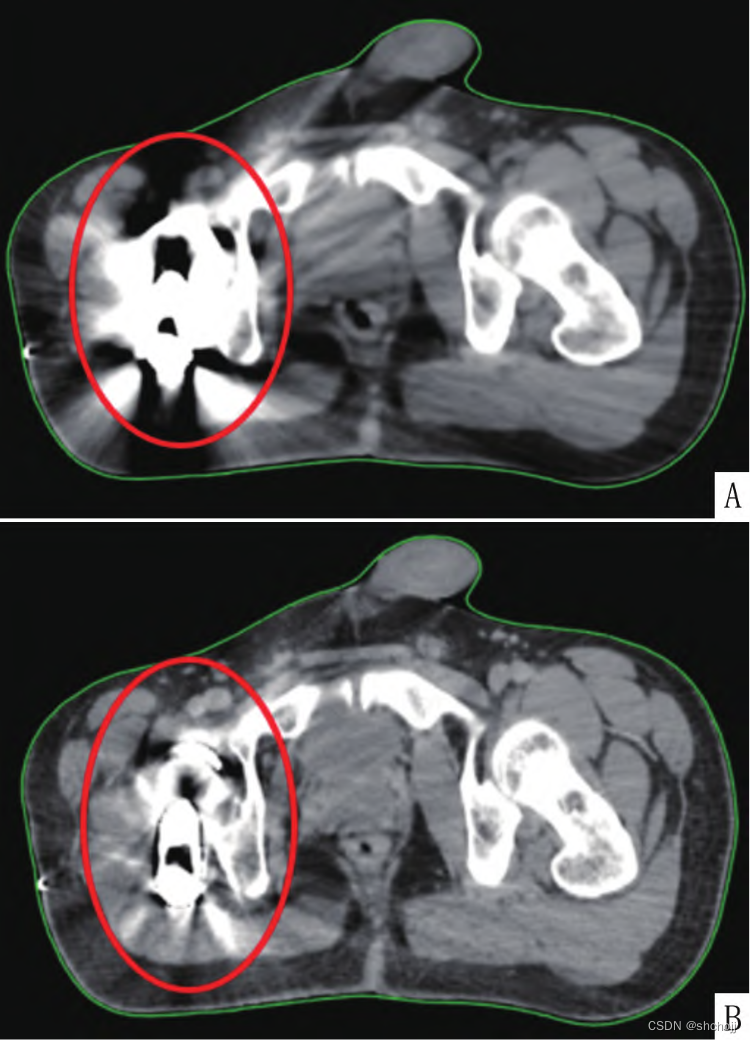

平扫CT(A),迭代算法去除伪影重建CT,实现低剂量扫描同时去除图像金属伪影(B)。需要询问物理师,电子密度是否正确,校正重建图像CT值的偏差是否在剂量计算容许误差范围内。